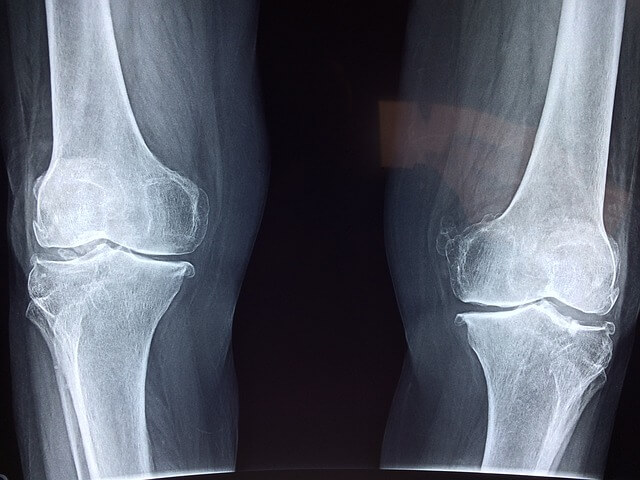

슬관절염

슬관절염은 슬관절 주변의 연골 파손 및 염증으로 인해 발생하는 관절염입니다. 이는 보통 연령이 들어갈수록 발생할 가능성이 높아지며, 통증, 강직성, 염증, 운동 장애 등의 증상을 유발할 수 있습니다.

무릎 퇴행성 변화

나이가 들면서 무릎 관절에 염증과 마찰이 생기는 것이 자연스러운 일입니다. 이러한 마찰은 무릎 통증, 강직성 등의 증상을 유발할 수 있습니다.